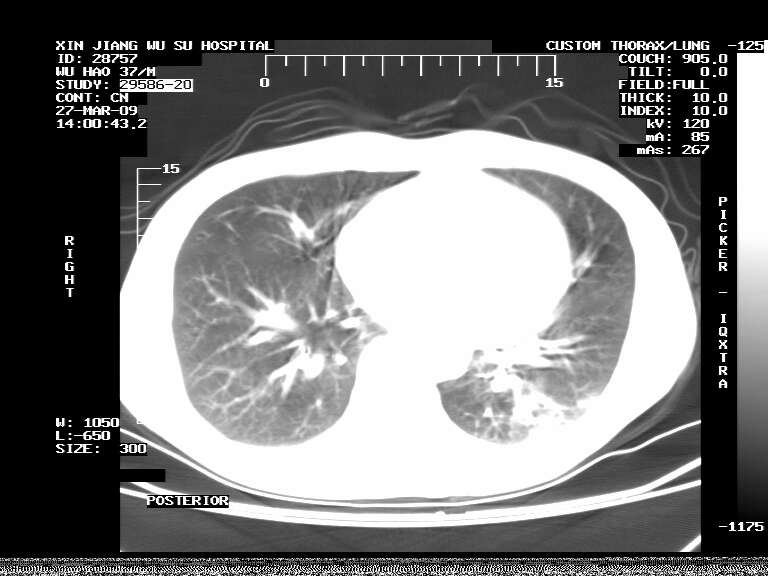

男,37岁,体检胸透发现阴影。

患者体检发现 无症状 左肺下叶占位,边缘模糊,可见血管聚束、分叶、胸膜牵拉,增强呈不均匀性强化。 首先考虑左肺下叶周围型肺癌,建议穿刺活检。

患者体检发现 无症状 左肺下叶占位,边缘模糊,可见血管聚束、分叶、胸膜牵拉,增强呈不均匀性强化。 首先考虑左肺下叶周围型肺癌,建议穿刺活检。支持!

左肺下叶见一结节病变,边缘欠清不光滑,与胸膜粘连且胸膜局限性增厚,注药后呈环形强化,动脉期壁呈明显点环状强化,静脉期壁强化减低,中心密度低无强化,灶周无明显的卫星灶和水肿区(晕征)---考虑周围性肺癌,不除外感染性病变,建议穿刺活检。

左肺下叶软组织病灶,密度较高,内见点状钙化,其周围见子灶,邻近胸膜扁平样增厚.c+病灶强化明显,中心强化弱.诊断:左肺下叶结核瘤.

周围有卫星灶,胸膜反应不明显,病灶中心有坏死。建议先抗结核治疗后,短期复查

左肺下叶大片实变影,内靠胸膜见不规则更高密度结节灶,边缘强化,相邻胸膜增厚,胸膜下脂肪线存在。考虑炎症,结核可能。